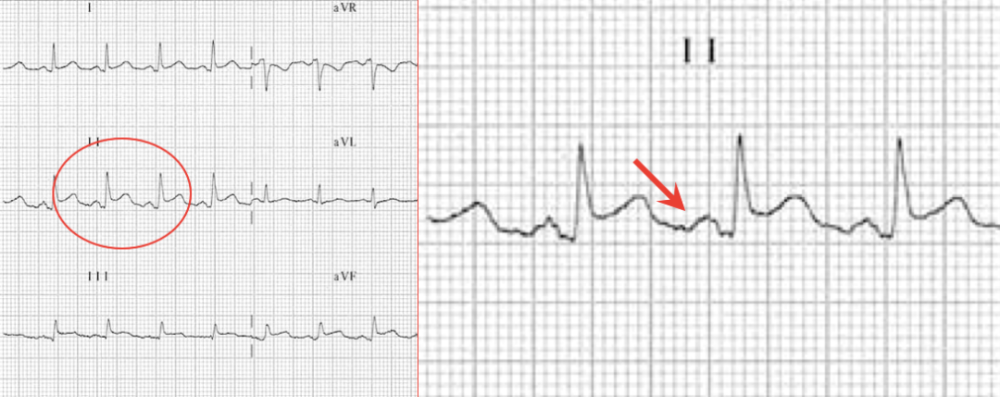

spodick征一种急性心包炎的特征性心电图

spodick征:一种急性心包炎的特征性心电图_腾讯新闻

心包炎的spodick征心电图